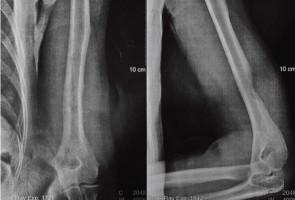

Using high-resolution micro-CT imaging, the researchers showed that the mice developed progressive spinal deformities beginning in adulthood, with vertebral changes closely resembling those seen in patients with NF1.